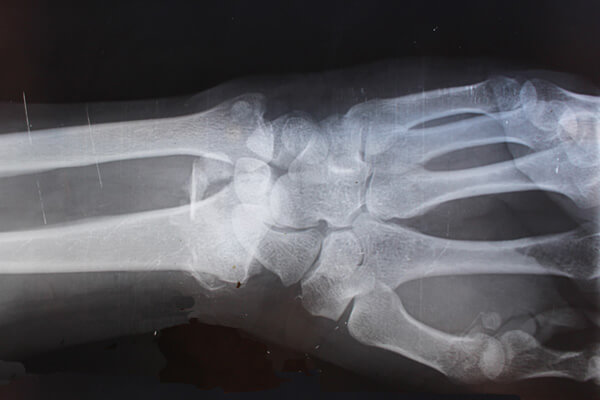

About the Auto Accident Case Lorem ipsum dolor sit amet, consectetur adipiscing elit. Integer commodo sapien felis. Pellentes faucibus sollicitudin ante,at porta felisrutrum eget. Sed ut nisl urna,e get convallis purus pretium facilisis. Interdum et malesuada. Lorem ipsum dolor sit…